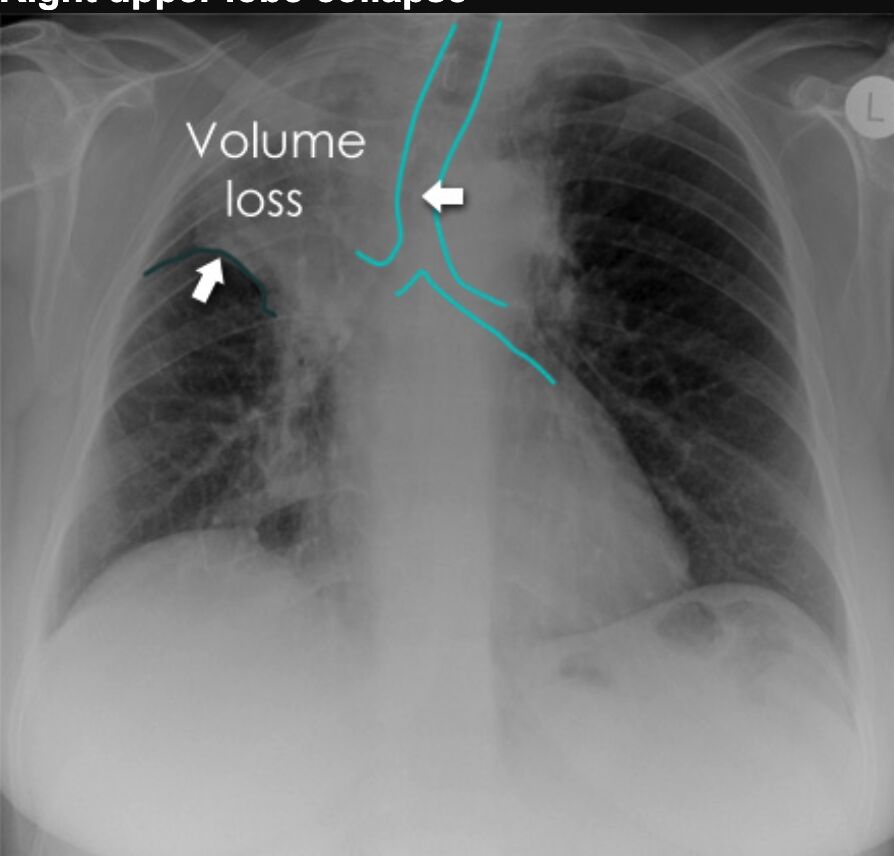

10.一個右上葉塌陷的病患,其胸部X光片會有那些改變?①右側肺門位置提高 ②氣管向左偏移

③右邊第一至第三肋間有較擁擠(crowding)的情形 ④上升主動脈和心臟右上緣輪廓會不清

(sihouette sign)

看這種肺部塌陷的X光要先知道幾件事

1. 一般情況的肺充滿空氣,所以X光看起來是黑的,一旦塌陷(collapse)之後

- 該處會變白色的,因為就只剩下肺部組織沒有空氣了

- 該處閒置的空間會變大,因為就跟氣球沒氣了一樣,所以可以預期氣管、肺門會往該處去

2. 肺門是什麼構造?就是中間交叉處

所以如果是右上葉塌陷

- 右上空間會變小,所以該處會變白色,氣管跟肺門都會往那邊去

- 其實刪去法把⓶刪掉就好了